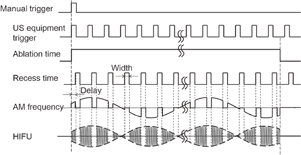

The transducer assembly was mounted on an arm and introduced into a water tank facing the target liver tissue, which was embedded in polyacrylamide gel. The acoustic properties such as sound speed and acoustic impedance of the polyacrylamide gel and water are almost identical. The porcine liver and polyacrylamide gel were degassed by a degasifier (SIBATA WJ-20). Polyacrylamide gel was constituted by mixing the materials shown in Table I. The HIFU transducer was excited at its central frequency by modulated bursts generated using three function generators (NF WF1974 and WF1946) and then amplified with a RF amplifier (E&I 2100). The schematic of the experimental setup for the LMI system is shown in Fig. 2. Figure 3 shows the timing diagram for the LMI experiment.

Standard image High-resolution imageFig. 3. Timing diagram for LMI.

Download figure: